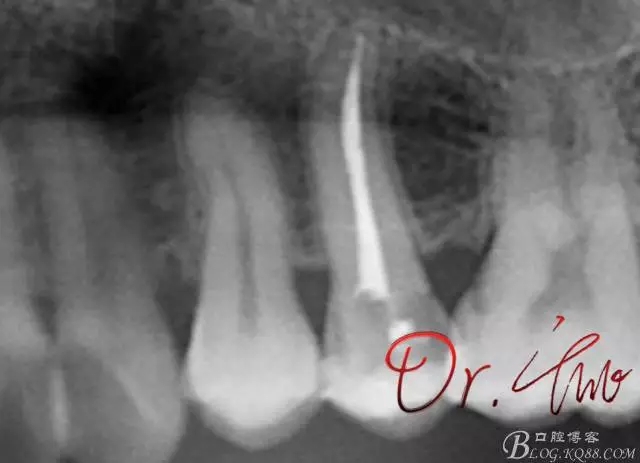

試主尖,近中頰側(cè)形成臺(tái)階

640.webp (7).jpg

試主尖,近中頰側(cè)再次拍片查看臺(tái)階位置及確定長(zhǎng)度

640.webp (8).jpg